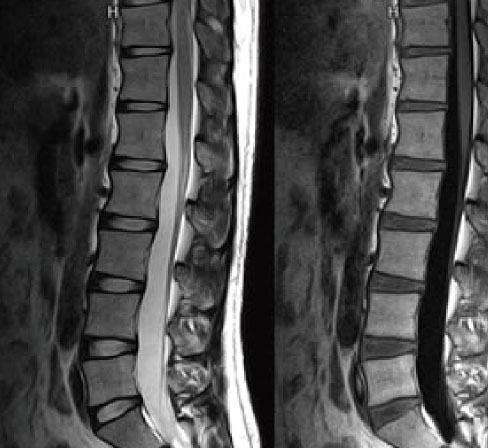

腰椎

MRI(Magnetic Resonance Imaging:磁気共鳴画像診断装置)検査は、強力な磁場の中で電波を身体に照射することで体内から放出される微弱な電波を受信し画像化する検査です。

身体の様々な断面や血管の撮影を行うことができます。検査時間は30分~1時間程度です。